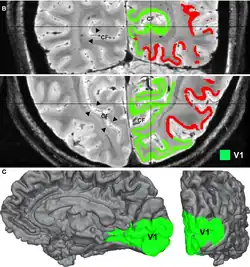

Adaptation is caused by the prolonged viewing of unchanging patterns. IOT in adaptation within the primary visual cortex has been explored. IOT as the ability to experience aftereffects in the eye that did not view the adapting pattern occurring in the primary visual cortex (V1) of cats. IOT may be mediated by callosal connections between the two hemispheres, and is not dependent on the conventional binocularity of neurons. The study attempted to provide the physiological evidence to the existence of IOT.[14] There is also FMRI evidence that observed binocular visual interactions in the visual cortex in humans.[15]